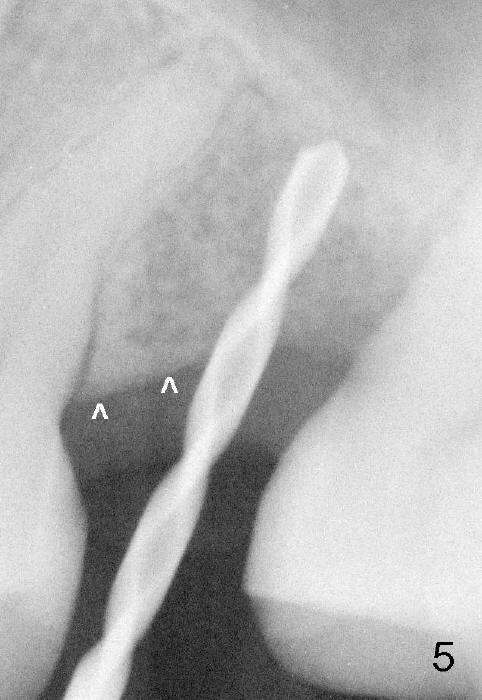

The mesial half of the crestal bone (Fig.5 ^) is denser than the distal half. There is a slope in the mesial crestal bone. As RPM for reamers is decreased, they tend to deviate to the least resistant area (distal, Fig.2). So does the implant (Fig.3).